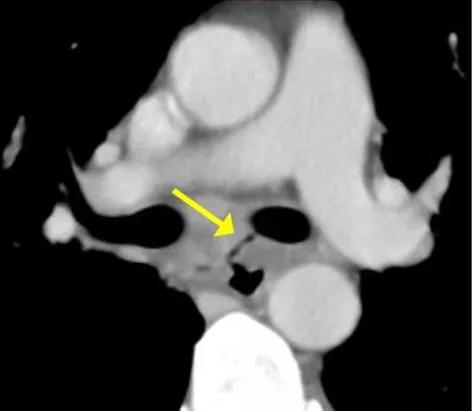

“片子再仔细看看,比较下纵隔窗,诶!纵隔这里,好像有几个气泡啊”,胡教授一边在大屏幕上带大家阅片一边分析:“像是个瘘,把食管和左主支气管联通起来了”。

“外院拍的片子都拿出来,看看之前有没有”。

历次的CT胶片一字排开,铺满了整整一面墙的读片灯。一张张看下来,发现最开始的CT上就有这个可疑的瘘,但是都太细太小了,不带着追溯的目的很难发现。